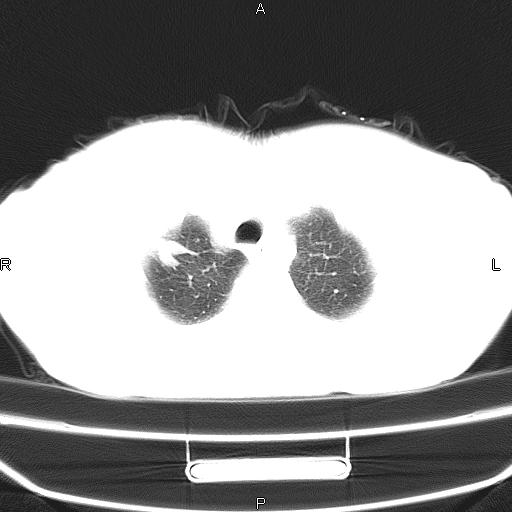

患者,女,66岁。健康体检胸部透视发现右上肺片状阴影。既往无不适,患者自诉三个月前曾有低热病史体温37.5左右一周。用药后缓解。至今无其它不适。请老师们指导指导。

考虑:右肺上叶周围型肺癌(分叶状肿块+砂粒状钙化+胸膜尾征)。

病灶见明显分叶、大小较大(大于3cm?),老年人,多考虑:肺癌,建议穿刺活检。

典型的中心型肺癌,尖段支气管阻塞。

以下是引用dyqct在2010-6-3 9:32:00的发言:[br]考虑:右肺上叶周围型肺癌(分叶状肿块+砂粒状钙化+胸膜尾征)。

不像中央型啊

周围性肺癌,

右肺上叶周围型肺癌可能性大。

考虑:右肺上叶周围型肺癌